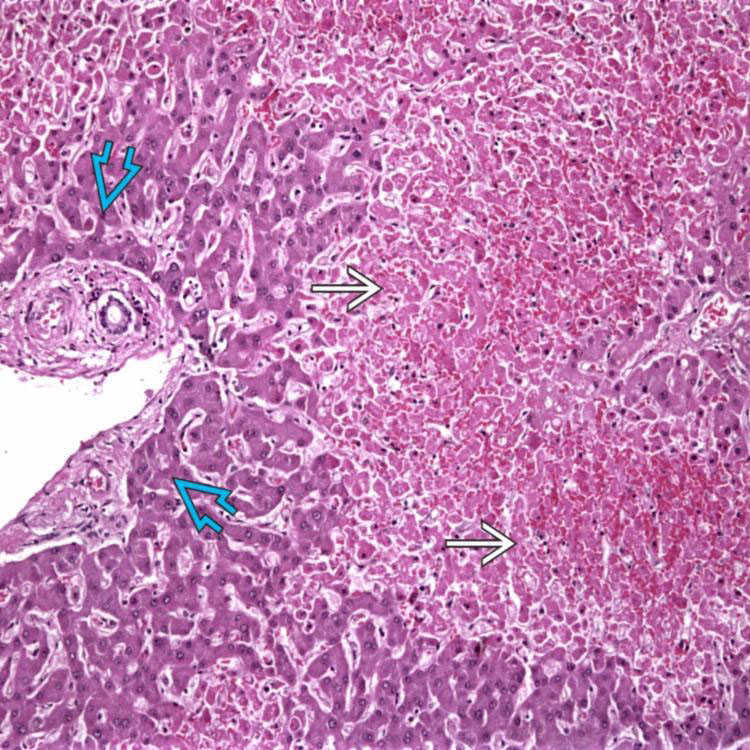

Cardiac (congestive) hepatopathy. (A) Gross photograph of a liver with Nutmeg Liver Hepatocytes A nutmeg liver appearance is due to a perfusion abnormality of the liver usually as result of hepatic venous congestion. Other causes include obstruction of blood flow in hepatic vein and inferior venacava. Nutmeg liver refers to the mottled appearance of the liver as a result of hepatic venous congestion. Can be seen in autoimmune hepatitis, drugs, chronic cholestatic conditions,. Nutmeg Liver Hepatocytes.